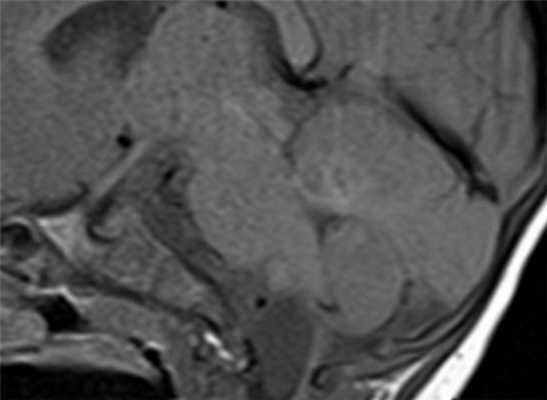

МРТ головного мозга. Корональная Т1-взвешенная МРТ. Многокамерные эхинококковые кисты.

- паразитарные кисты